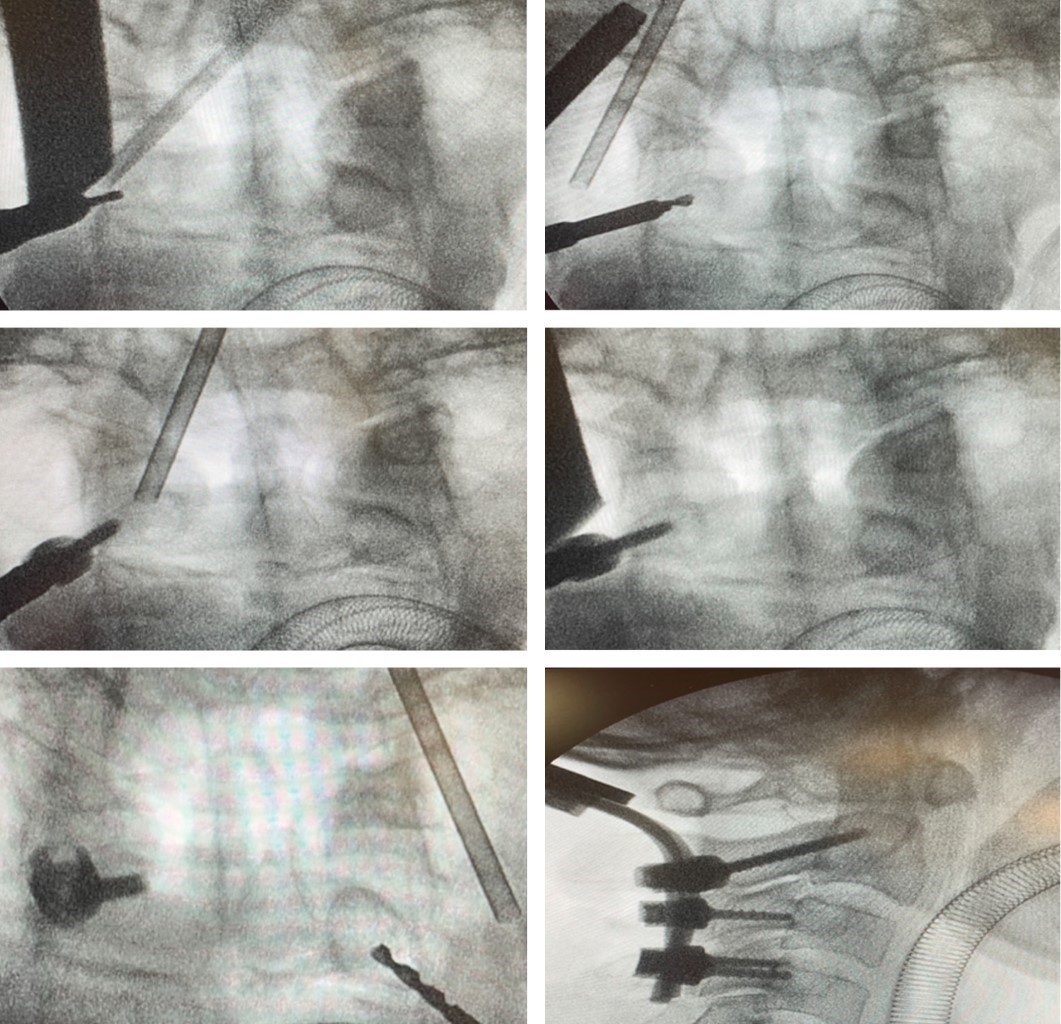

Un punto que consideramos importante es que el tornillo no debe pasar la porción medial de la carilla articular superior por riesgo de perforar la cortical anterior del cuerpo vertebral y lesionar estructuras anteriores (Figura 3). Recomendamos realizar el estudio tomográfico de control en el mismo día de la cirugía y evaluar la posición de su tornillo (Figura 4).

Se utilizó la clasificación de Lee y cols. para determinar el tipo de arteria vertebral intraaxial: tipo A-0; 7 arterias vertebrales (AV) derechas, 7 AV izquierdas, tipo B-1; 6 AV derechas, 6 AV izquierdas, tipo C-2; 3 AV derechas y 1 AV izquierda. A todos los pacientes se les realizó estudios tomográficos de columna cervical simple postquirúrgica para evaluar la posición de los tornillos transpediculares en C2 y se utilizó la clasificación por grados de Neo y cols. De 28 pedículos instrumentados la posición tomográfica postquirúrgica fue de 28 en el grado 0.

Figura 4